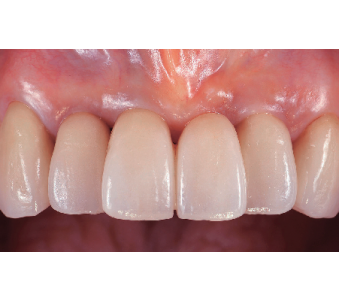

결과로 증명합니다.

국제모아치과의

실제 임상 증례